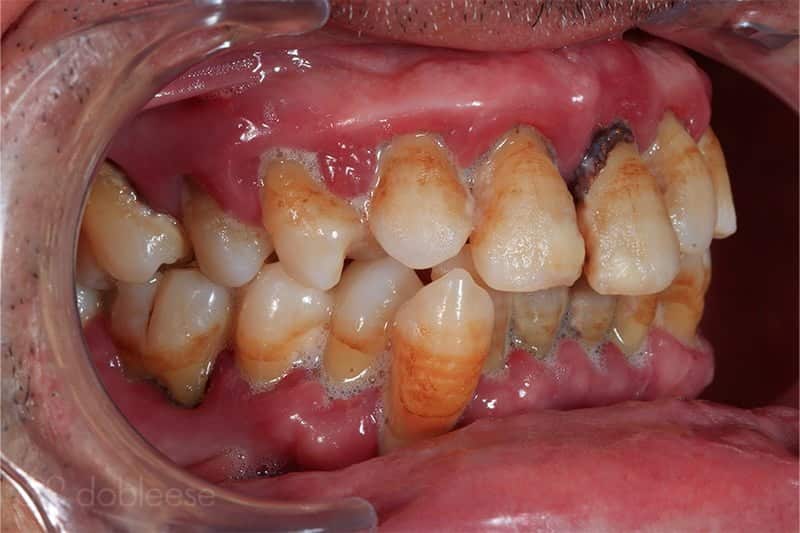

Juan Ramón llegó a nuestra clínica tras recibir la recomendación de un familiar, al que le hicimos un tratamiento muy parecido. Llegó a Dobleese con tanta movilidad en las piezas dentales, que no podía comer con normalidad porque sufría el riesgo de perderlas al masticar alimentos duros.

Al estudiar su caso, observamos que tenía una enfermedad periodontal muy agravada con gran pérdida de hueso alrededor de los dientes, motivo por el cual se le movían tanto. Por ello, concluimos que no podíamos mantener ninguna de las piezas dentales, ya que todas estaban en mal estado, con infección y con una pérdida de soporte imposible de recuperar.